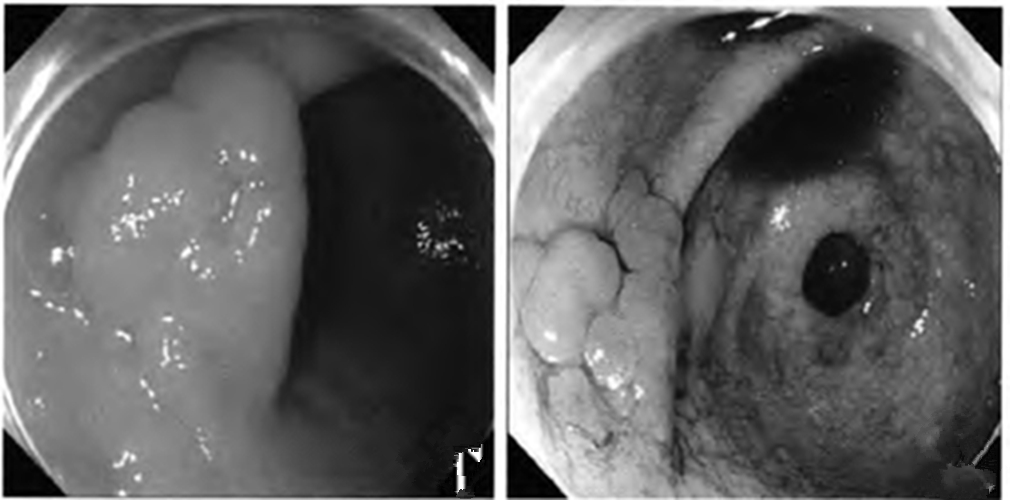

慢性胃炎圖片

慢性胃炎

慢性胃炎的

成人慢性胃炎

中型淺表萎縮慢性胃炎

萎縮淺表性慢性胃炎

萎縮性的慢性胃炎

萎縮性慢性胃炎

萎縮慢性胃炎

萎縮出血性慢性胃炎

輕型淺錶慢性胃炎

輕型淺表型慢性胃炎

縮的慢性胃炎

淺表型慢性胃炎怕

淺表型慢性胃炎

淺表型慢性胃炎萎縮

淺表型糜爛出血慢性胃炎

淺表型糜爛慢性胃炎

輕型慢性胃炎

淺表型慢性胃炎發發

淺表型慢性胃炎好